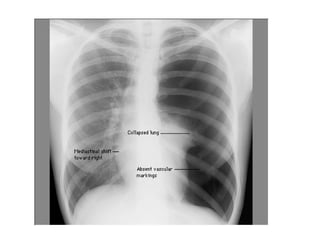

Citez cinq causes pouvant expliquer la détresse

respiratoire aiguë de Monsieur L. (par argument de

fréquence)?

Surinfection bronchique

Pneumopathie infectieuse

Autre infection

Embolie pulmonaire

Insuffisance cardiaque gauche

Pneumothorax

Prise de médicaments sédatifs